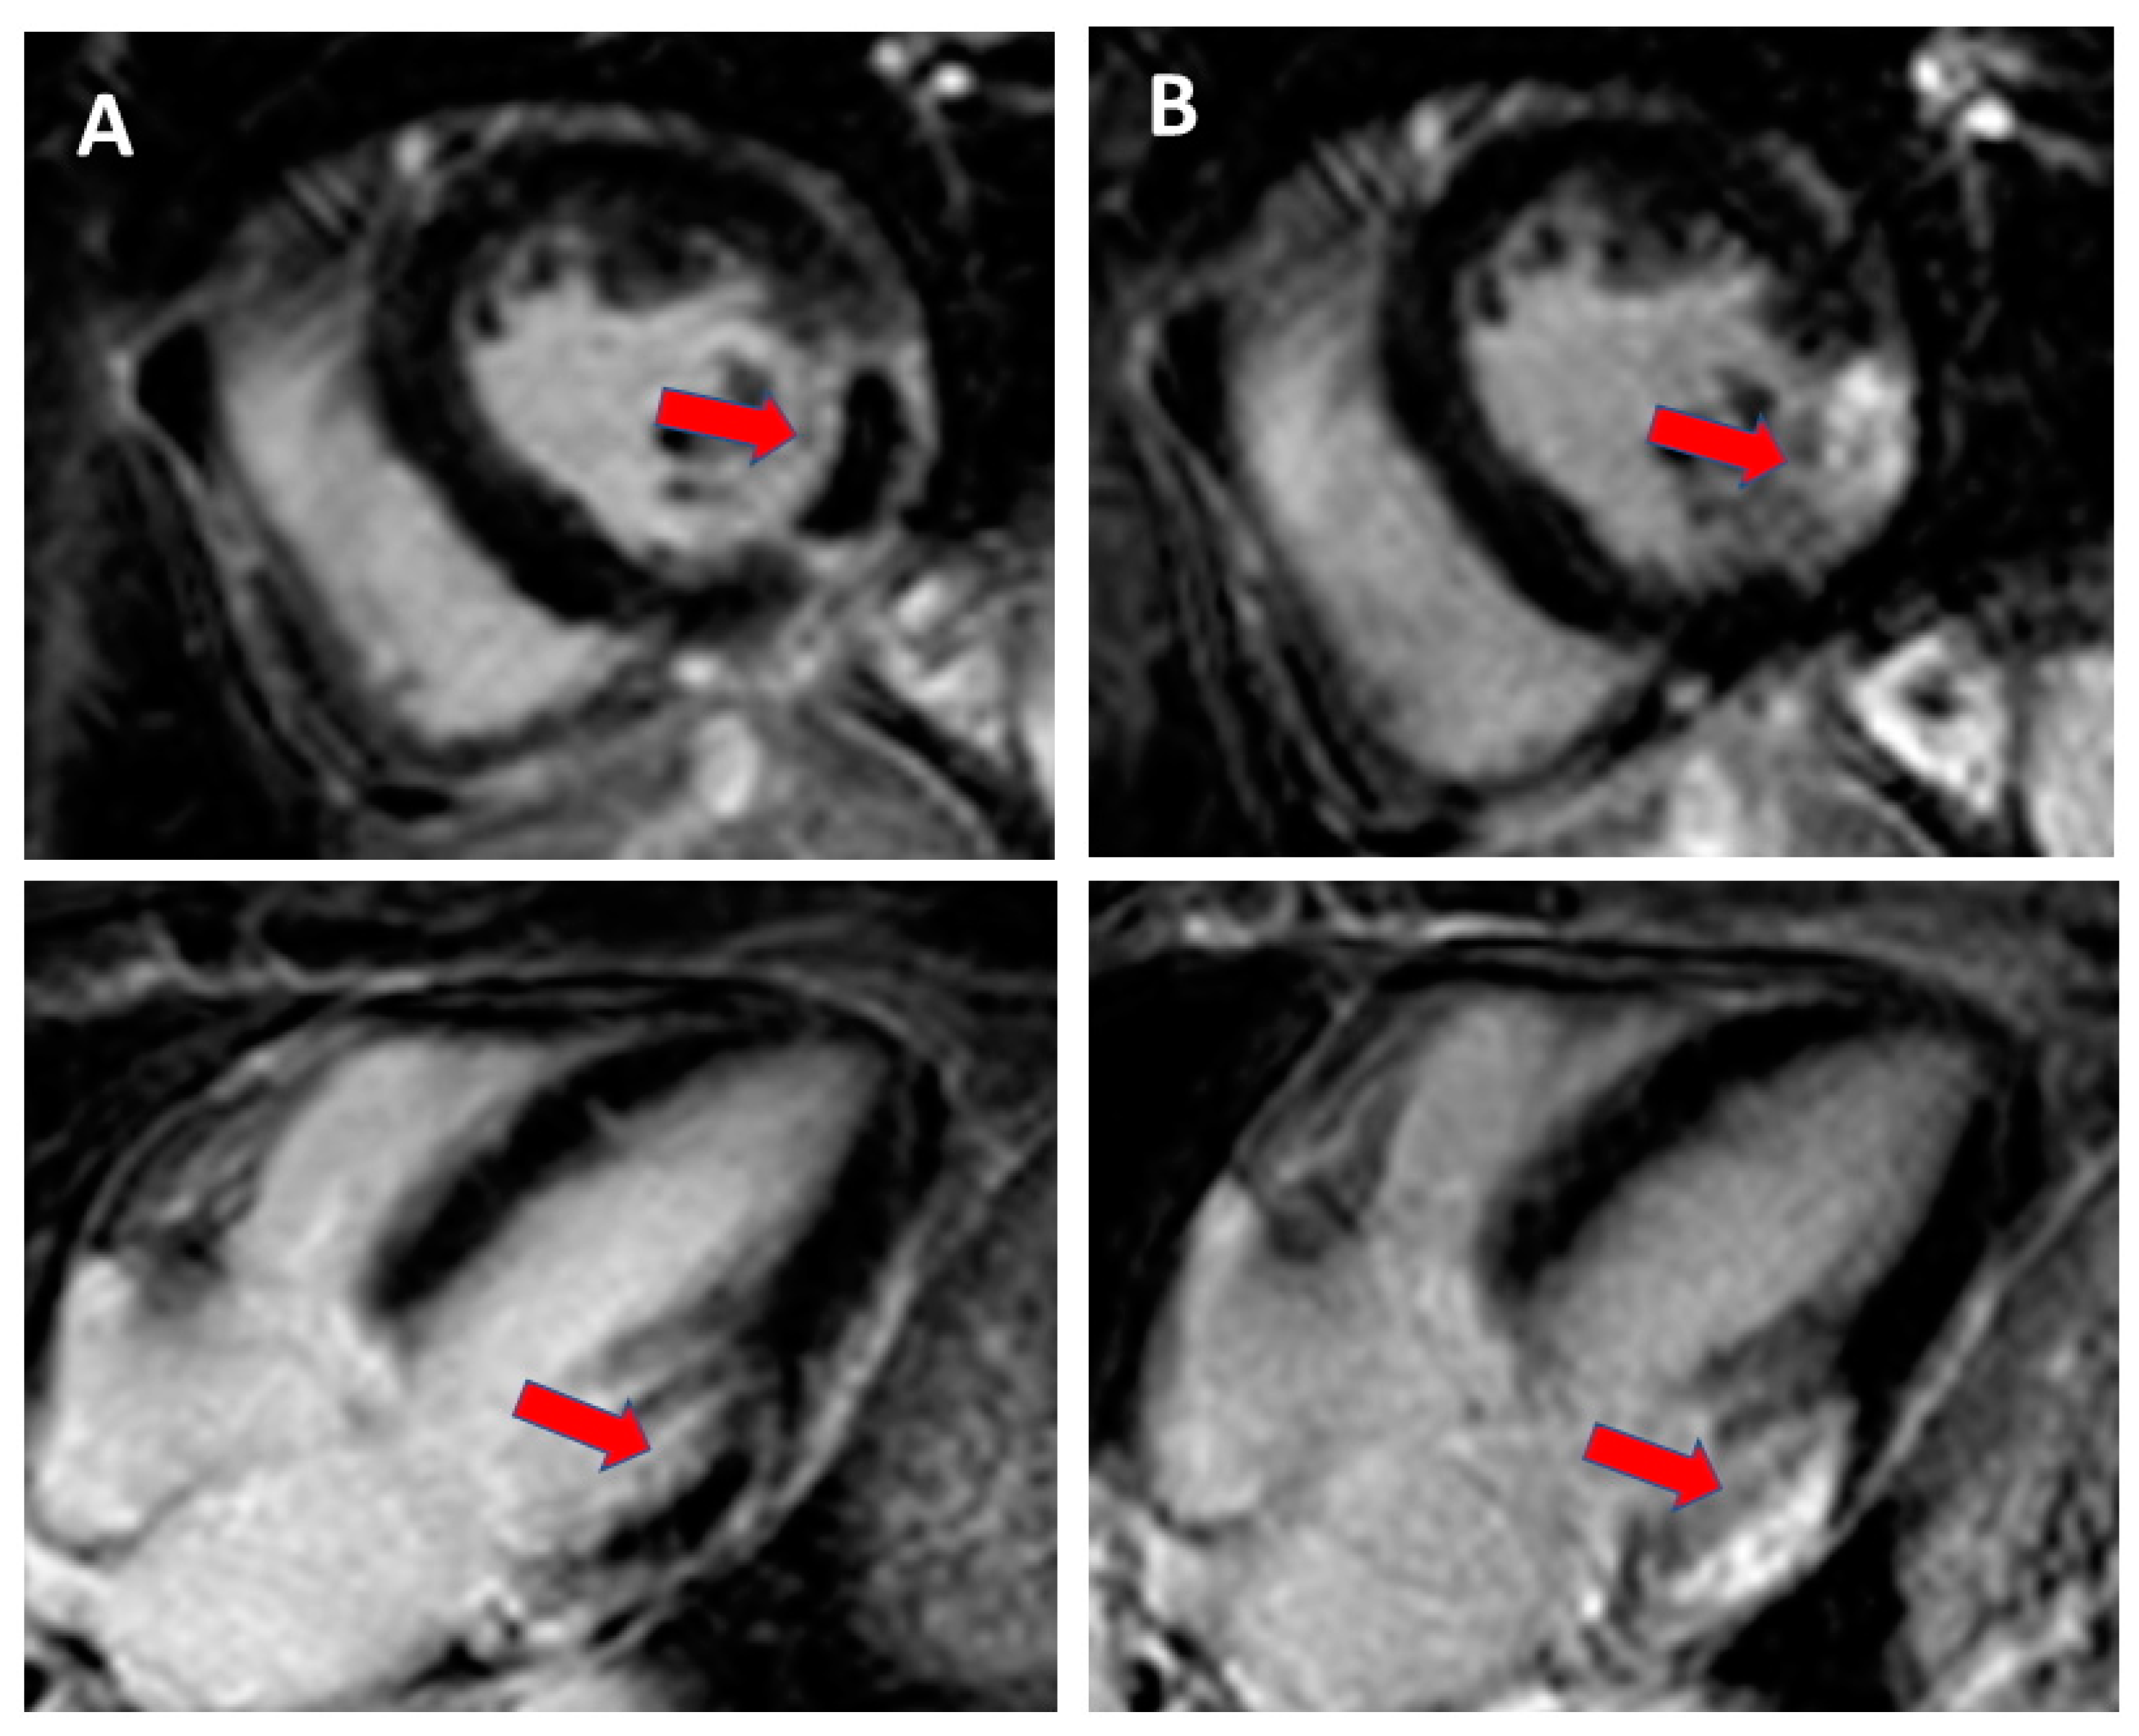

CMR with late gadolinium enhancement can provide information on the entity and localization of scarred myocardium with high accuracy [12]. Figure 3 and Figure 4 show examples of CMR with late gadolinium enhancement imaging for scar identification in myocardial infarction. Leyva et al. [30] investigated the use of late gadolinium CMR before CRT implantation, showing that pacing LV scarred myocardium was associated with high risk of cardiovascular death, hospitalizations for heart failure, and death from any causes. Conversely, in the study by Taylor et al. [31], LV lead positioning over non-scarred LV segments, as assessed by late gadolinium enhancement CMR, was associated with better LV reverse remodelling and clinical outcomes at follow-up.

Figure 3.

Cardiac magnetic resonance with late gadolinium enhancement (LGE) imaging for scar identification in myocardial infarction (MI): (A). day 1 after MI with no-reflow area (red arrow) and (B). day 14 after MI with scarring (red arrow).

Figure 4.

Cardiac magnetic resonance with LGE imaging in a mid/apical subendocardial myocardial infarction (red arrow) in (A). short axis mid ventricular view and (B). two chamber view.